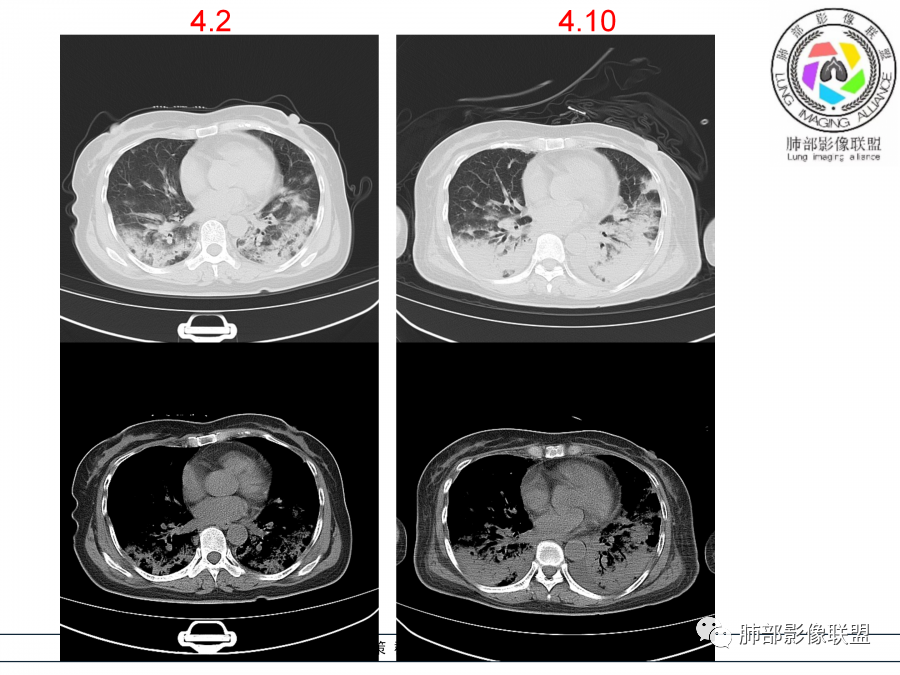

影像,第一次双肺中下叶胸膜下多发斑片状实变影,部分融合成,周围散发磨玻璃影,磨玻璃影内可见小叶间隔及小叶内间隔增厚,病变平行于胸膜,第二次间隔8天,双肺实变影明显进展,有重力作用,支气管近端堵塞,进展较快,临床有发热,血沉高,狼疮SLE阳性,考虑1:OP(机化性肺炎)2:SLE相关肺炎,建议支气管镜灌洗液病原学检测。

第一次双肺中下叶胸膜下多发斑片状磨玻璃及实变影,病变平行于胸膜,支气管通畅,8天后,双肺实变影明显进展范围扩大,部分支气管近端堵塞,进展较快,胸腔积液,抗感染治疗无效,考虑:非感染性疾病:结缔组织相关性肺病。鉴别机化性肺炎。